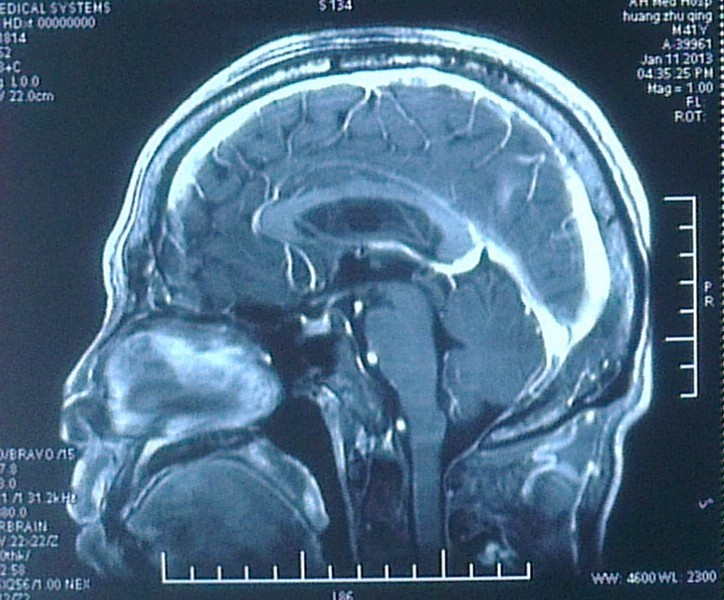

三脑室占位 (术前) (术后)

据了 解,我院神经外科自上世纪九十年代在省内率先开展神经内镜工作以来,在颅底解剖及临床辅助应用方面发挥了极其广泛和重要的作用。并使我科神经内镜水平始终 保持全国先进、省内领先水平。尤其在去年八月份购置省内第一台高清内镜以来,单纯神经内镜下手术更是得到了“井喷”式的应用。除常规开展内镜下单鼻孔经蝶 窦入路鞍区肿瘤切除术等术式外,脑室内病变的治疗更是上了一大台阶。率先在省内开展了单纯神经内镜下三脑室上部肿瘤切除、鞍上池囊肿切除及复杂脑积水治疗 等手术。其治疗效果佳、创伤小、恢复快。据王斌主任介绍,此类术式在全省尚属首次,填补了我省内镜下进行脑室内病变手术的空白,使我院神经外科内镜水平处于全国领先地位。